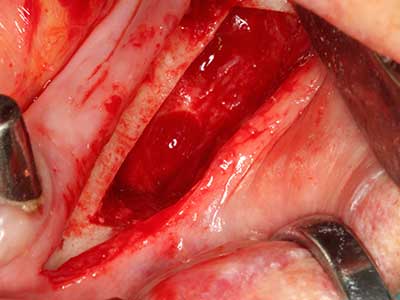

Fig. 18: Preparation of a cortical cover with the piezo bone saw (Piezomed, W&H).

Fig. 19: Surgical site after neurolysis and removal of osteoma.

Fig. 20: The removed bone cover is re-adapted and fixed with an osteosynthesis screw (KLS Martin, Tuttlingen).